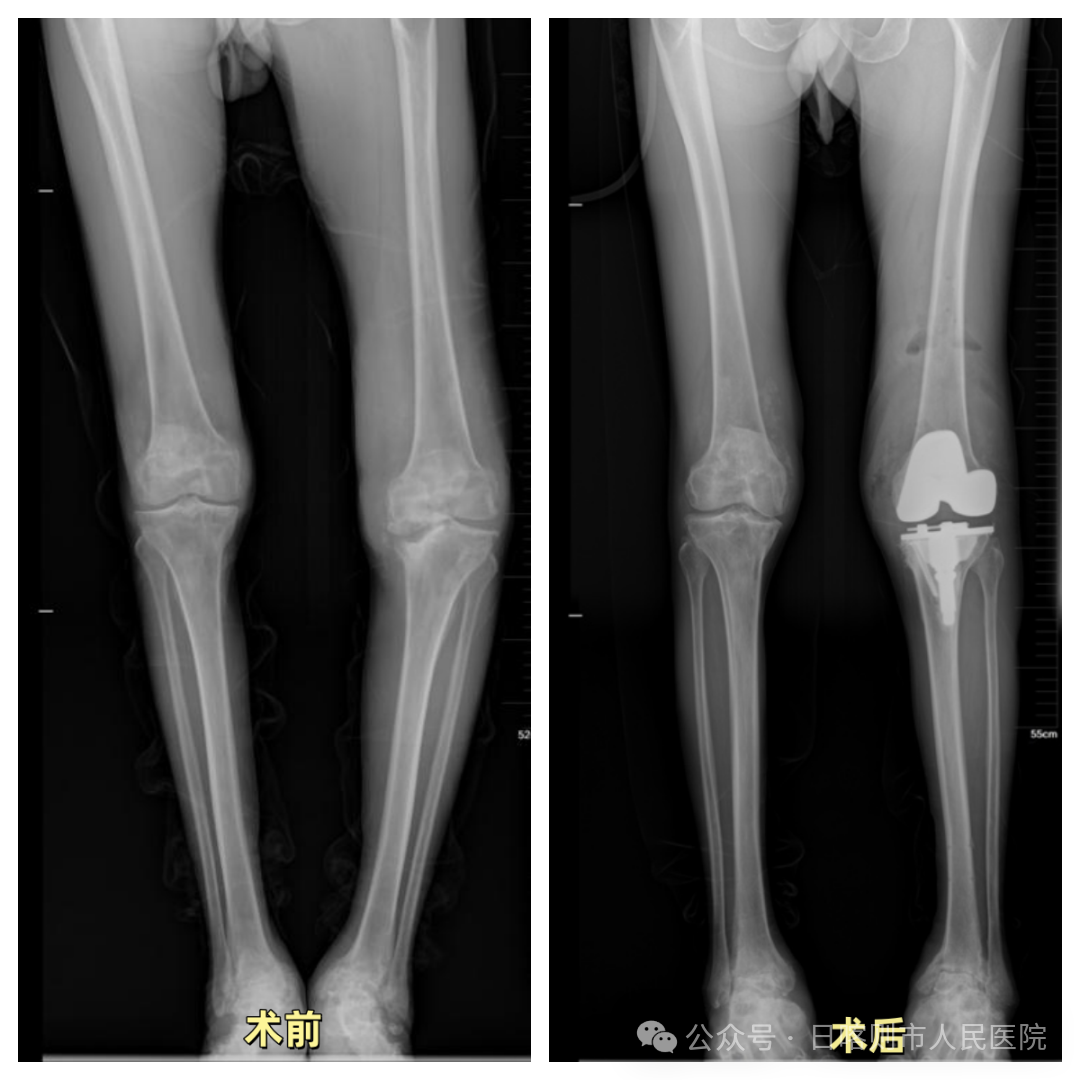

▲典型病例2:60余岁男性,左侧膝骨关节炎,膝内翻合并胫骨近端骨缺损